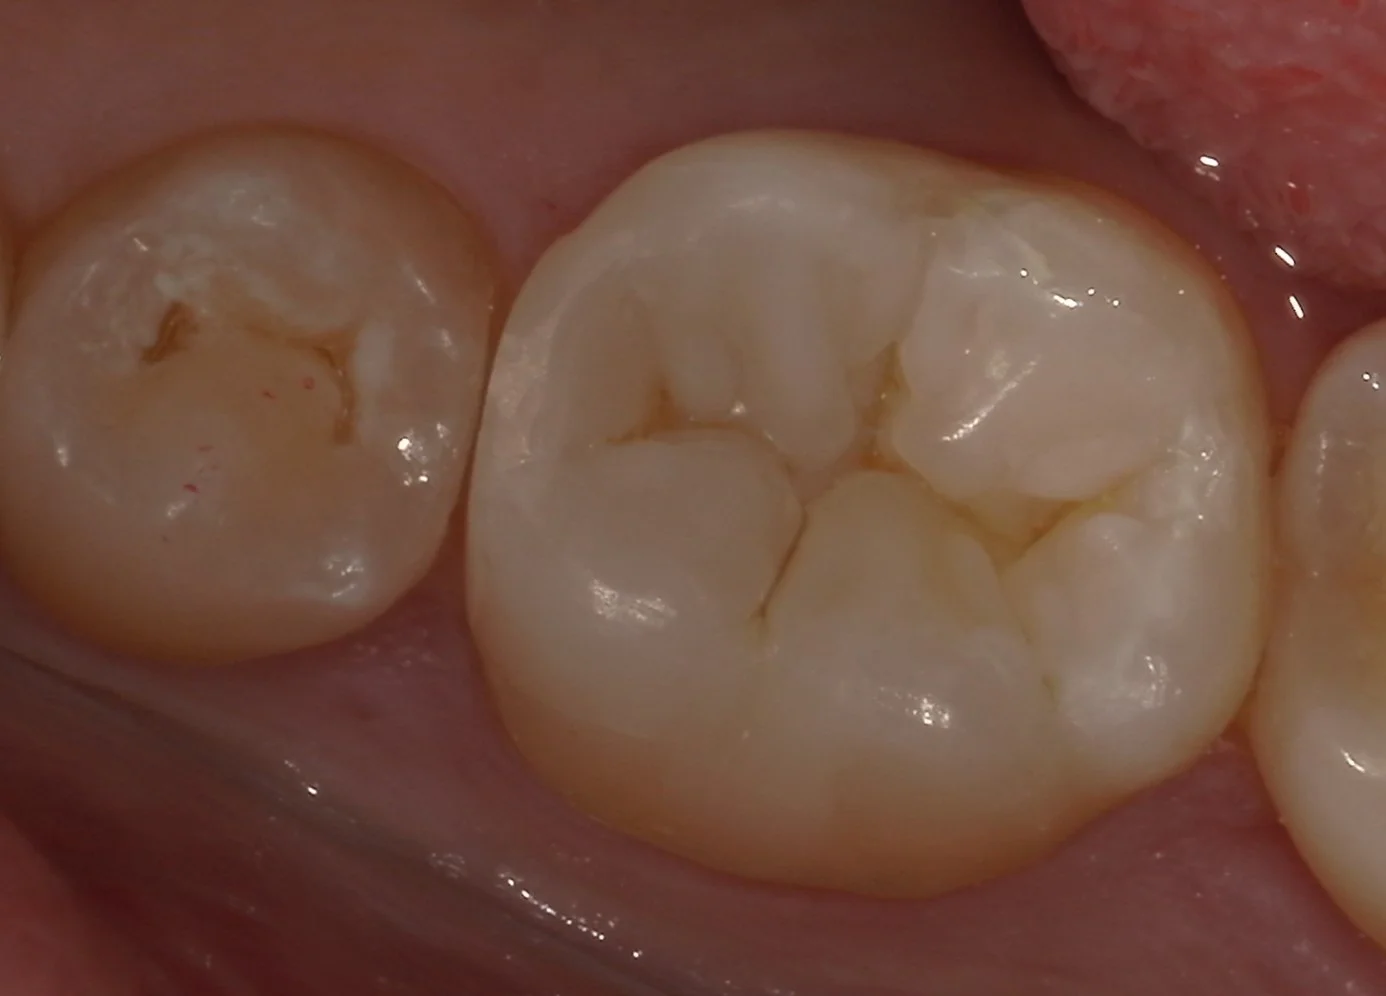

では術前の写真からです。

今回治療を行うのは画面中央の金属の詰め物が詰まっている部分です。

適合が悪く、歯茎の下から大きく中に虫歯が入り込んでいるような状況になっていました。

そして詰め終わったのがこちらです。

割と違和感なく詰められたかと思います。